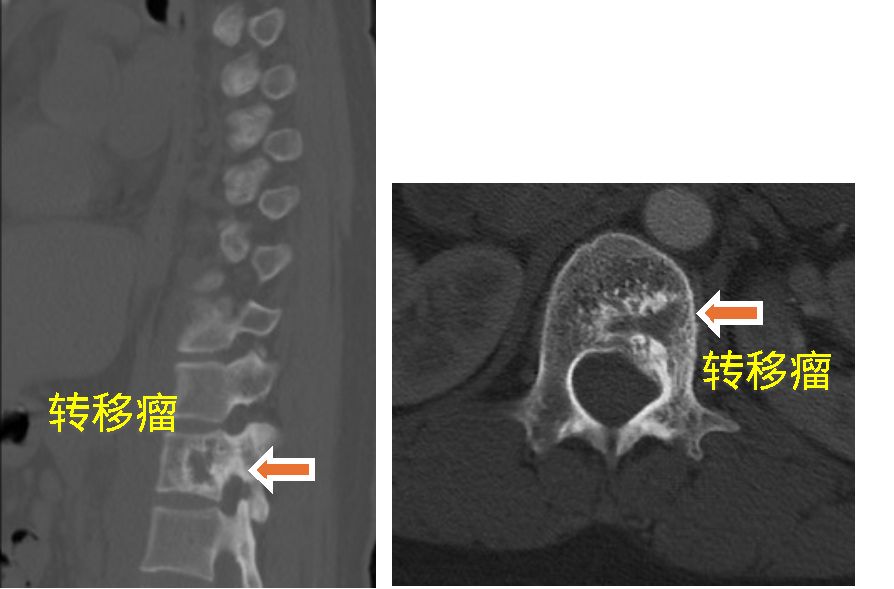

患者一、前列腺癌胸椎脊柱转移行骨水泥注射肿瘤灭活及镇痛术

患者因前列腺脊柱转移导致严重背部疼痛,行骨水泥注射后疼痛完全消失。